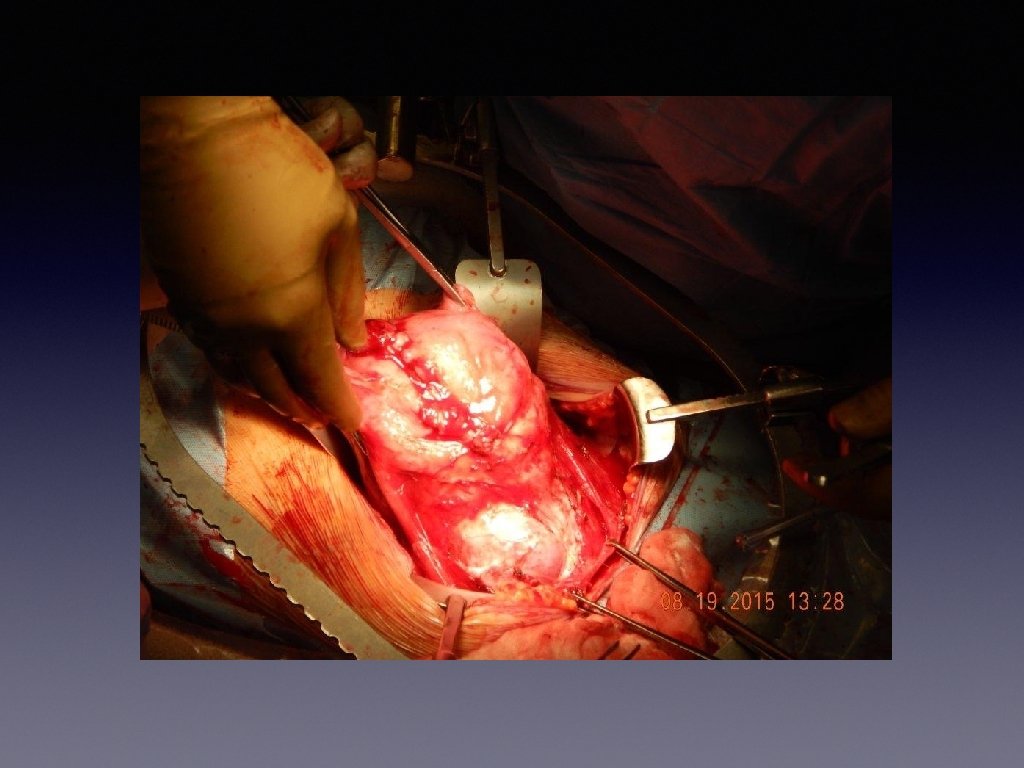

Unsuspected Placenta Perceta

Management of Unexpected Placenta Percreta (discovered at time of laparotomy) Delay uterine incision if anatomy appears abnormal • • Distorted or ballooned lower uterine segment • Blood vessels on uterine serosa • Invasion into bladder or surrounding tissue • Assess location and extent of placental invasion visually and by ultrasound • Evaluate for presence of active bleeding • Inquire about available resources: blood/blood products, surgical assistance and equipment.

Management of Unexpected Placenta Percreta (discovered at time of laparotomy) If the patient is stable and the facility is not currently prepared: • • Cover the uterus with warm laparotomy packs and await assistance and supplies before proceeding with operative intervention or • • Close fascial incision, place staples in skin, and consider transfer to tertiary facility with experience in management of perorate If the patient is actively bleeding, apply local pressure to bleeding areas (other than areas where placental tissue is at risk), then prepare for hysterotomy for delivery followed by surgical or conservative mangement of placenta percreta.